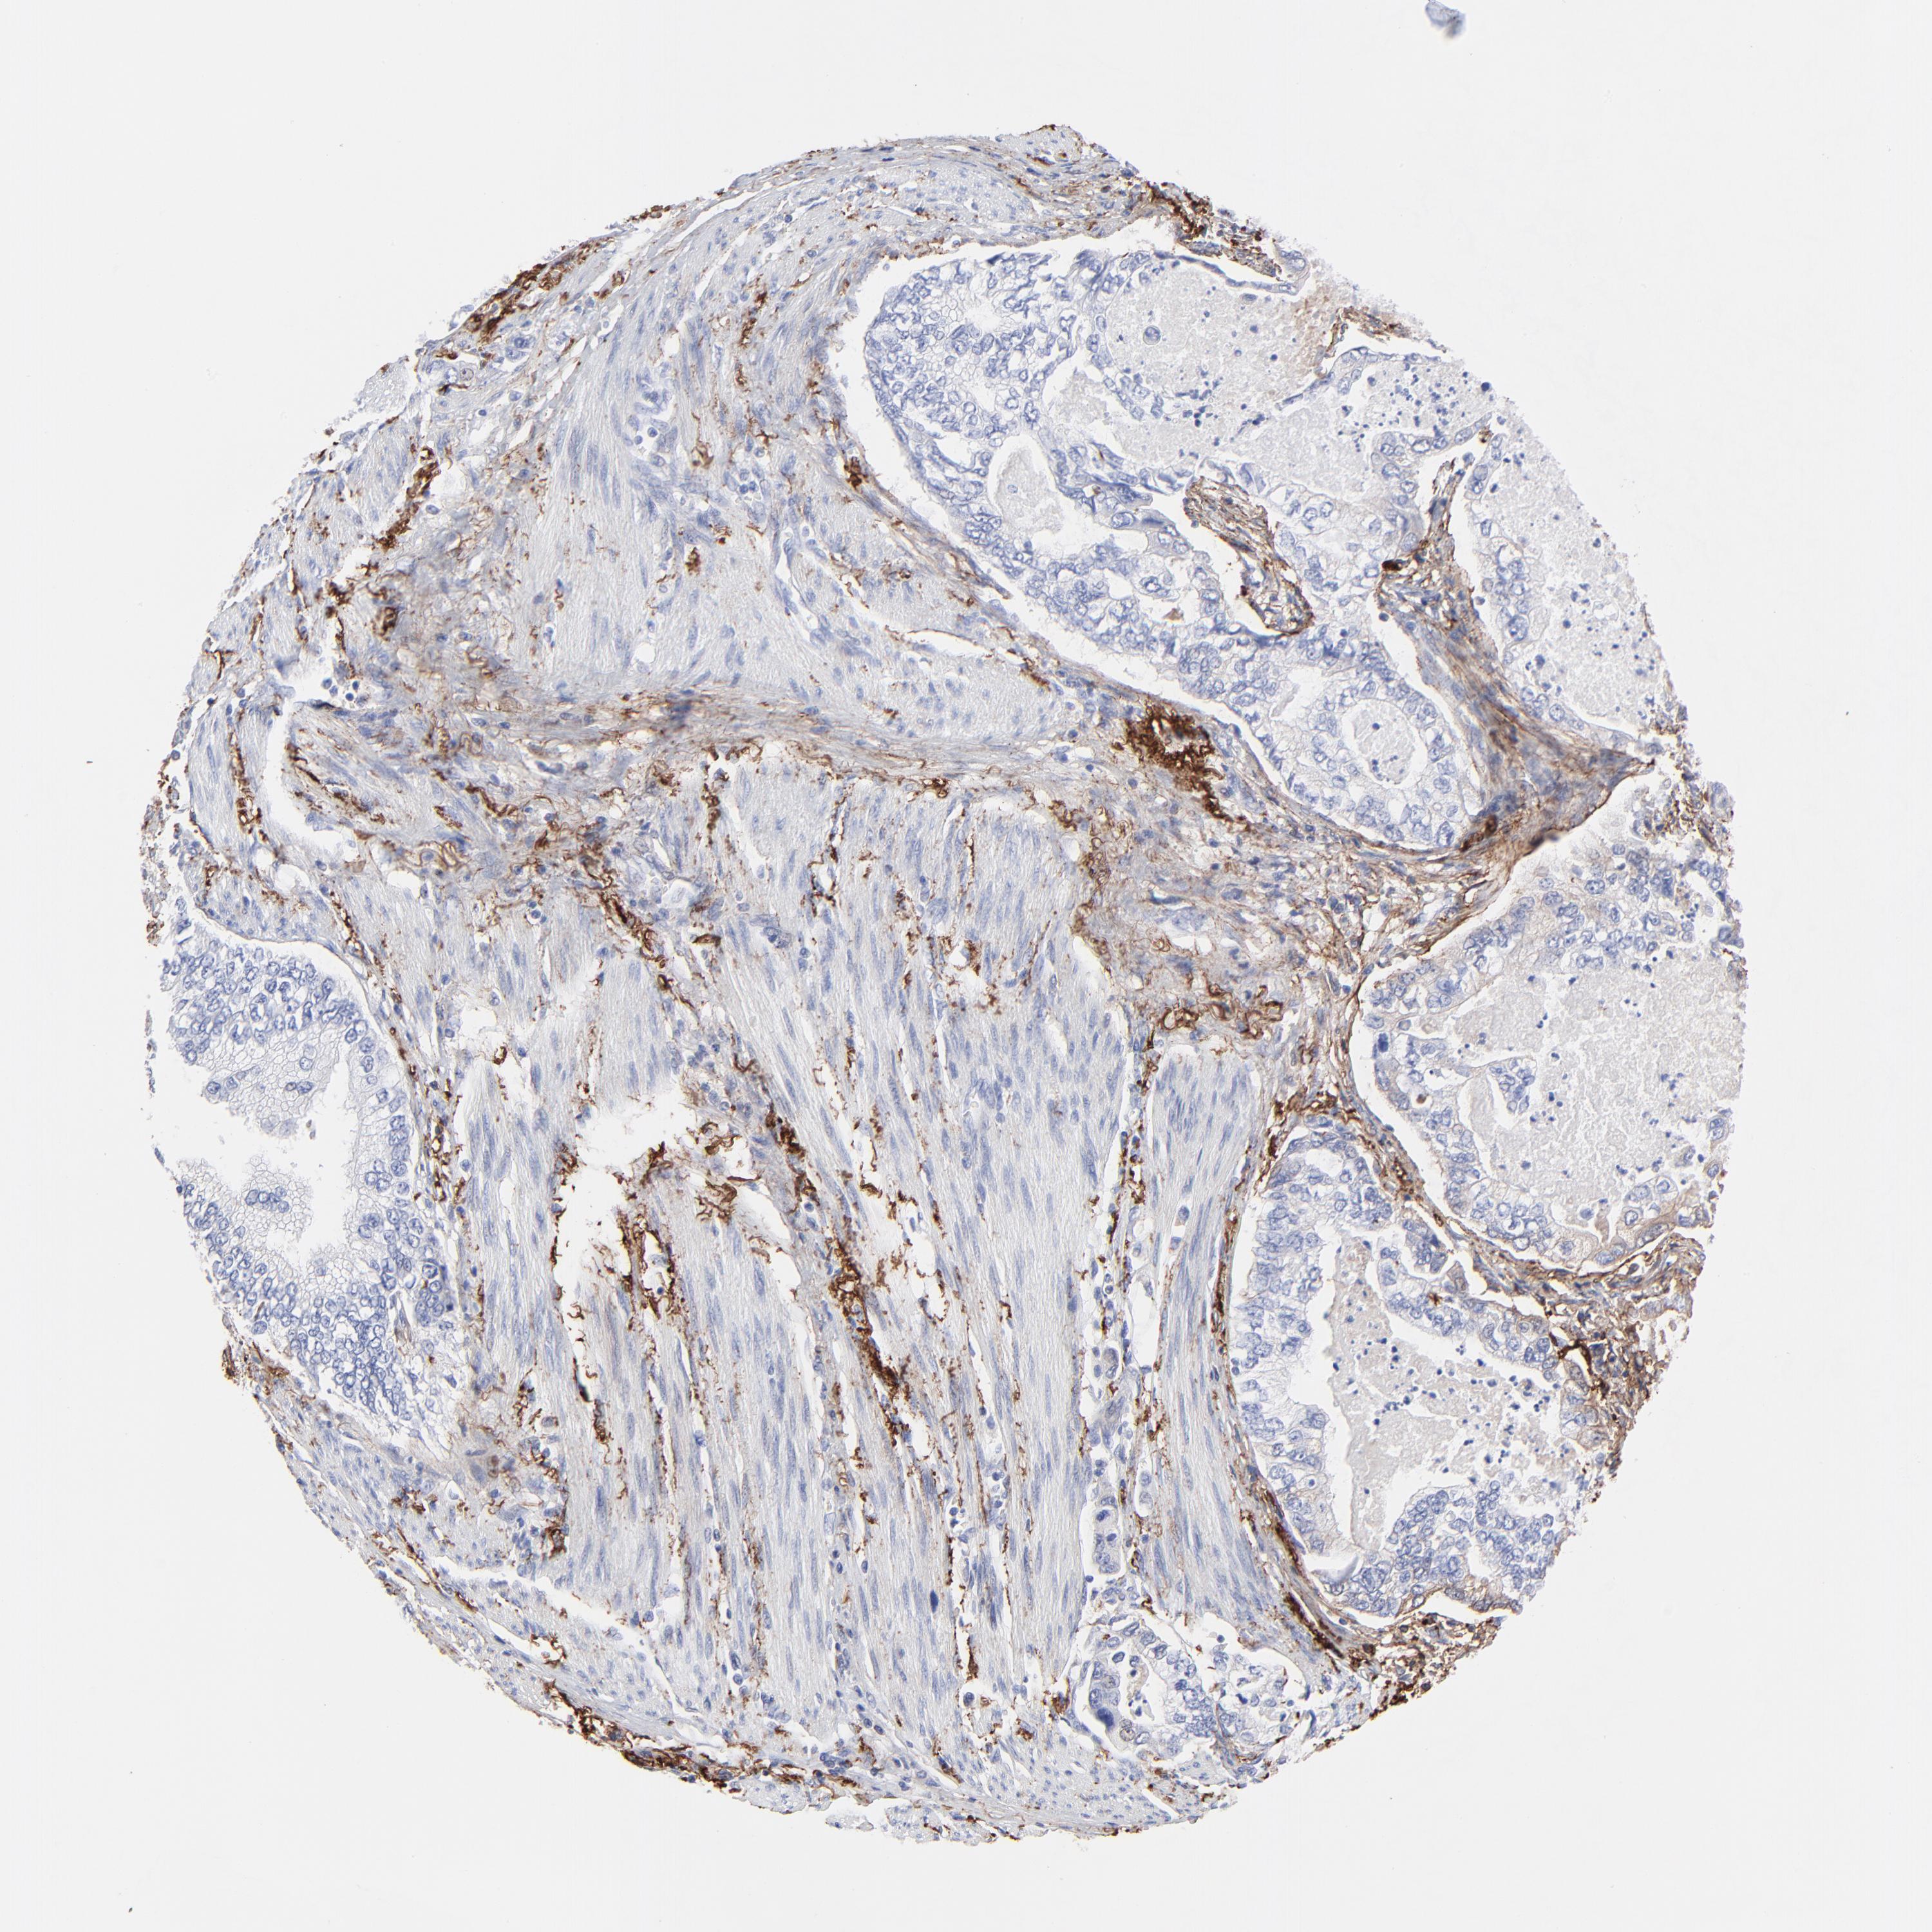

STOMACH CANCER - Protein expressioni

A mouse-over function shows sample information and annotation data. Click on an image to view it in a full screen mode. Samples can be filtered based on level of antibody staining by selecting one or several of the following categories: high, medium, low and not detected. The assay and annotation is described here.

Note that samples used for immunohistochemistry by the Human Protein Atlas do not correspond to samples in the TCGA dataset.

Antibody stainingi

Antibody staining in the annotated cell types in the current human tissue is reported as not detected, low, medium, or high, based on conventional immunohistochemistry profiling in selected tissues. This score is based on the combination of the staining intensity and fraction of stained cells.

Each image is clickable and will lead to virtual microscopy that enables deeper exploration of all samples and also displays staining intensity scores, fraction scores and subcellular localization as well as patient and tissue information for each sample.

Antibody HPA001934

Antibody CAB018622

Staining

High

Medium

Low

Not detected

Intensity

Strong

Moderate

Weak

Negative

Quantity

>75%

75%-25%

<25%

None

Location

Nuclear

Cytoplasmic/membranous

Cytoplasmic/membranous,nuclear

Adenocarcinoma, NOS